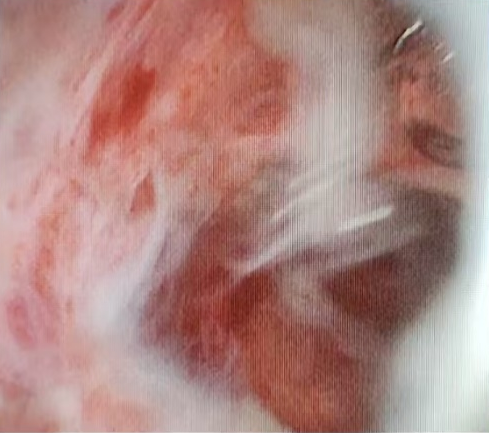

当天,在麻醉科主任医师、医学博士谢文静和副主任医师王冠男的舒适麻醉及内镜中心马瑞卿护士配合下,李振涛操作内镜顺利进入十二指肠降部,发现该部位一巨大黏膜下隆起,同时乳头口白色脓液流出,随乳头插管切开后大量脓液涌出,十二指肠黏膜下隆起迅速消退,胆总管亦清理出一枚成形结石,反复清理胆道确认无结石残留后沿导丝置入一次性胆道子镜,子镜顺利进入胆囊管及胆囊,可见胆囊管及胆囊壁水肿充血明显,腔内大量脓苔、脓液残留,经反复冲洗吸引,患者胆囊高张状态解除,再经内镜中心及麻醉团队娴熟配合,顺利为患者完成ERCP取石及胆囊减压冲洗术,手术全程耗时40分钟,术后当日患者腹痛症状迅速解除,压痛反跳痛症状完全消失。

胆囊冲洗出大量脓液